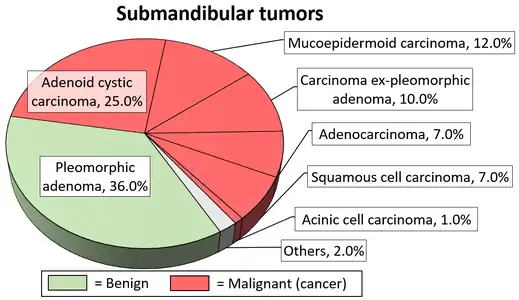

The benign tumors of the submandibular gland is treated by simple excision with preservation of mandibular branch of the facial nerve, the hypoglossal nerve, and the lingual nerve.[17] Other benign tumors of minor salivary glands are treated similarly.

Diagrams by Mikael Häggström, MD - 1 2 3 4 5 Psychogios G, Bohr C, Constantinidis J, Canis M, Vander Poorten V, Plzak J, et al. (January 2021). "Review of surgical techniques and guide for decision making in the treatment of benign parotid tumors" (PDF). European Archives of Oto-Rhino-Laryngology. 278 (1): 15–29. doi:10.1007/s00405-020-06250-x. PMID 32749609. S2CID 220965351.